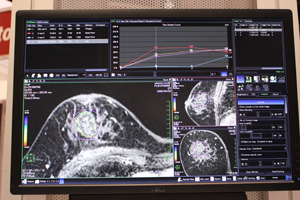

●Wash-out Map(FDA未申請)

Wash-out Map

Wash-out Mapは,腫瘍を造影して信号値が上がったあとに,どの程度wash-outするかを評価する機能で,従来のダイナミック造影解析ソフトウェアに搭載される。悪性のしきい値はピークからは−20%と規定されているが,評価結果を視覚化することで,腫瘍のどの位置が悪性度が高いと想定されるかが明瞭になり,生検における悪性度の高い部分の採取を支援する。